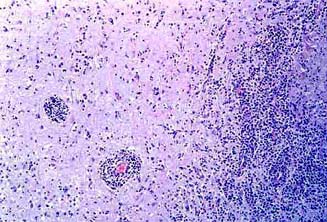

ESTREPTOCOCIA: Meningoencefalitis purulenta.